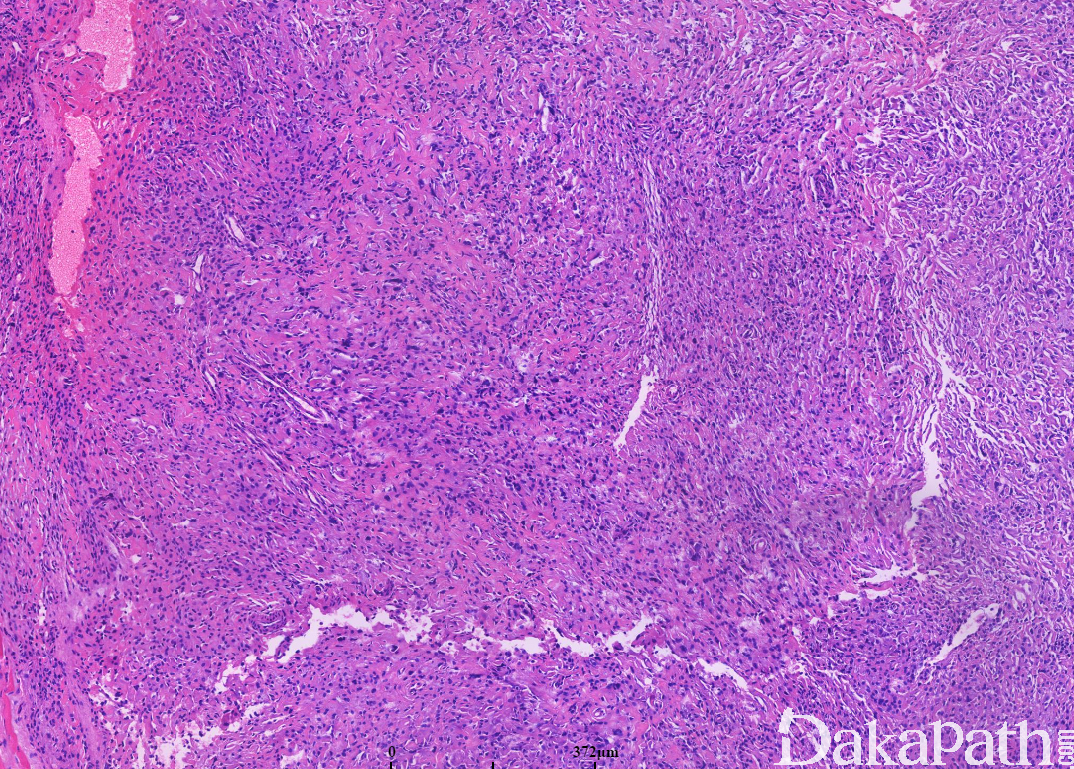

好发于成年人的头颈部,肿块周界清晰,呈圆形或分叶状;

低倍镜下肿瘤呈界限清楚的小叶状结构,小叶内见圆形或多边形细胞紧密排列,间质稀少;